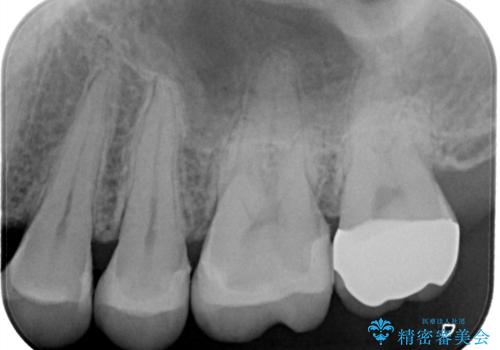

一番奥の歯は銀歯に覆われている範囲が多いため、強度などを踏まえ被せ物にしました。

その他2本は詰め物です。

銀歯が綺麗な白い歯になりました。

適合がとてもよいので、フロスの引っかかりも解消されました。